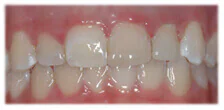

After